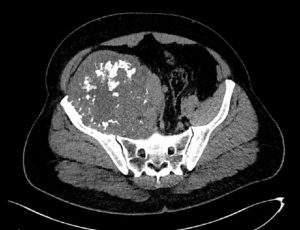

Це історія, яку неможливо забути. Молодий чоловік. Велика пухлина тазової кістки. Складна локалізація, високий ризик та мінімум шансів на просте рішення. Було проведено складну операцію – радикальне видалення пухлини з реконструкцією тазу за допомогою індивідуального 3D-друкованого імпланта. Це був шанс зберегти рух та якість життя. Через 10 місяців виникло інфікування. Довелося видалити імплант разом із кінцівкою. Але ця історія не про поразку. Пацієнт повернувся до активного життя, керує автомобілем і зараз проходить підготовку до екзопротезування. Онкохірургія – це не завжди про ідеальний сценарій, але завжди про можливість вибороти життя і рухатись далі.